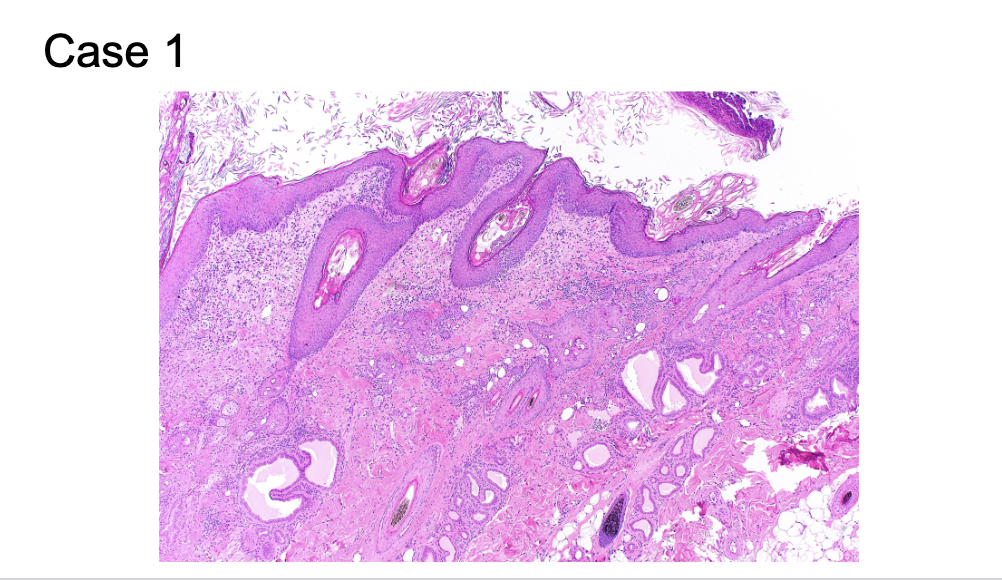

What are features of chronic

1. The crusts contain degenerate neutrophils, keratin, serum, and

few colonies of cocci

2. Diffusely moderately hyperplastic and mildly spongiotic with lymphocytic

exocytosis.

3. Superficial dermis is infiltrated by a moderate number of perivascular mast cells, lymphocytes, plasma cells, neutrophils, and eosinophil (mast cells).

4. Thickening of skin (acantosis)

Acantosis - thickening of the epidermis